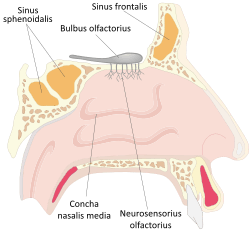

The frontal sinuses are situated behind the brow ridges. Sinuses are mucosa-lined airspaces within the bones of the face and skull. Each opens into the anterior part of the corresponding middle nasal meatus of the nose through the frontonasal duct which traverses the anterior part of the labyrinth of the ethmoid. These structures then open into the hiatus semilunaris in the middle meatus.

Paranasal sinuses Nose diagram

Nose diagram- Frontal sinus